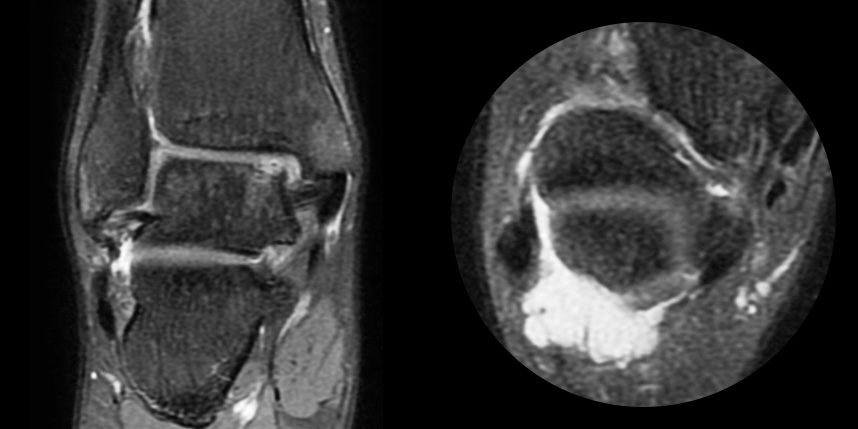

연골손상의 단계를 결정할 때 사용하는 ICRS 단계에서 3단계 미만의 연골손상에 사용하는 방법으로 울퉁불퉁한 표면을 다듬어 주는 정도의 수술법입니다.

4단계 이상일 경우 미세천공술을 기본으로 시행하며, 미세천공술로 나온 본인의 골수줄기세포와 함께

연골 생성을 촉진할 수 있는 “재료”를 같이 주입하는 치료를 시행합니다.

손상된 연골 부위에 작은 구멍을 뚫어 골수에서 나오는 줄기세포를 이용하여 연골 재생을 유도하는 방법으로 근본적으로 섬유연골(정상연골보다는 약한 연골)로 재생된다고 알려져 있습니다.

특수하게 농축하여 제작된 6% 콜라겐(리젠실603) 또는 9% 콜라겐(이엔카티)을 천공술을 시행한 부위에 덮어 주어 미세천공술 단독보다 좋은 치료 결과를 기대할 수 있습니다.